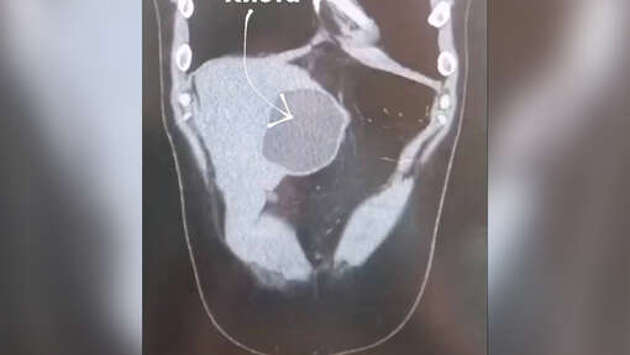

В Подмосковье врачи спасли 29-летнего пациента, у которого нашли кисты с яйцами ленточных червей. Об этом сообщает Минздрав региона. Мужчина обратился к медикам с многочисленными жалобами. У него наблюдались сильные боли в животе и диарея. Помимо этого, у человека не было аппетита, после употребления жареного, жирного или острого его рвало. Во время исследований выяснилось, что в печени молодого человека появились три новообразования с паразитами, одна из кист могла вскоре лопнуть. "Такое развитие событий грозило не только распространением яиц ленточных червей по организму больного, но и перитонитом", – поделились в ведомстве. Специалисты провели операцию, которая длилась три часа. Во время вмешательства из мужчины извлекли 10-сантиметровые новообразования. На данный момент россиянин проходит медикаментозное лечение. По словам специалистов, эхинококкоз может проявляться даже спустя несколько лет после заражения. Медики предположили, что паразиты попали в организм пациента во время поездки на Филиппины, где он мог съесть мясо экзотического животного-носителя.